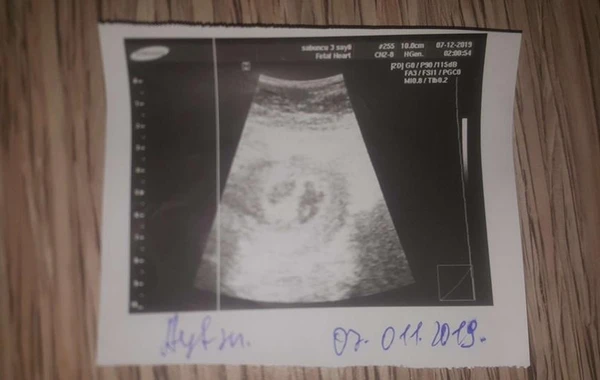

Şikayətçi iddia edir ki, hamiləlik dövründə aparılan müayinələrə əsasən, əkiz övlad gözləyib. Lakin təbii doğuşdan sonra onun bətnində bir dölün olduğunu bildiriblər.

"İlk dəfə həkimə gedəndə 6 həftəlik hamilə olduğumu və əkiz övladımın olacağı deyildi. Ondan sonra karantinə görə bir neçə dəfə USM-ə düşə bildim, çox gedə bilmirdim.

Hamısında da deyildi ki, əkizdilər. 9 ayın tamamında sancılarım başladı və təcili yardımla xəstəxanaya aparıldım. Orada məni Xatirə adında həkim doğuşa qəbul etdi.

Doğuşdan öncə iki dəfə ürək döyüntülərini yoxlamaq üçün aparat qoşdular. Hər ikisində də əkiz uşaqların olduğuna əmin oldular. Sancım çoxalandan sonra doğuşa alındım.